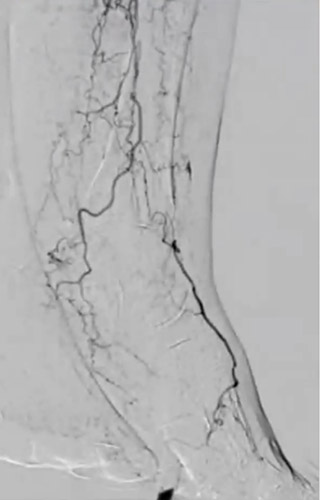

同側順行アプローチにて造影を行うと前回治療したPA(Peroneal Artery)は開存しており、ATA(Anterior Tibial Artery)は入口部から閉塞していた(図1)。末梢部分のDA(Dorsal Artery)は確認出来た(図2)。